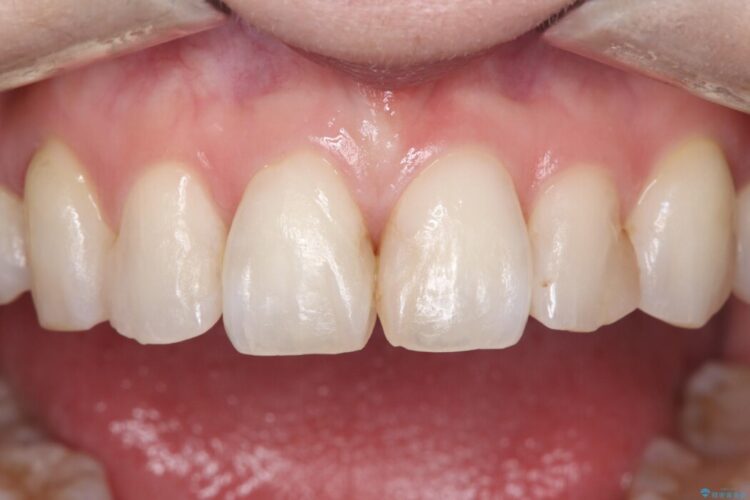

欠けて変色した前歯をオールセラミックで美しく

欠けて変色した前歯をオールセラミックで美しく ビフォー 欠けて変色した前歯をオールセラミックで美しく アフター

上の前歯4本が、過去の治療による変色や欠けで見た目が気になるとご来院されました。